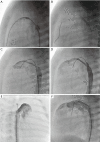

Figure 3

Patient with aortic valvular stenosis. (A) Aortic angiography depicts doming of the aortic valve, diameter of the valvular hinges is measurable. Note the angiographic jet, which can serve as guide for crossing of the wire. A pacing catheter is placed in the RV for rapid pacing; (B) balloon valvuloplasty with 6 mm × 20 mm low-pressure balloon under rapid pacing (Tyshak Balloon, PFM, Cologne, Germany).